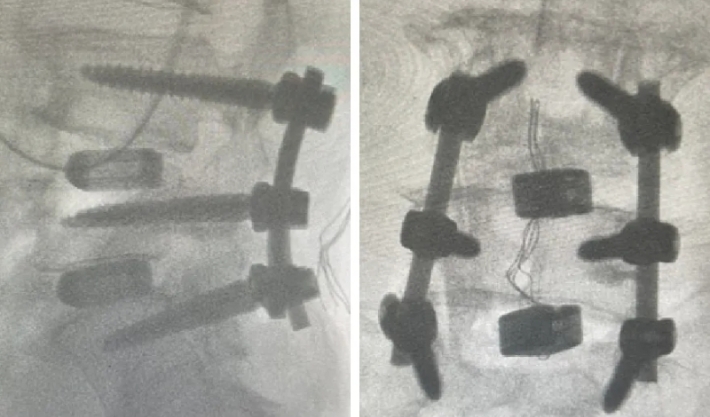

近日,beat365中文官方网站第六附属医院(新疆维吾尔自治区骨科医院)脊柱外三科在医疗技术上取得新的突破,成功为两位腰椎手术患者利用3D打印融合器实施了腰椎椎体间融合术,患者术后恢复良好。

随着人口老龄化趋势不断加剧,腰椎间盘突出症、腰椎管狭窄症、腰椎滑脱等已成为常见的退行性脊柱疾病之一,严重影响中老年人的生活质量和身心健康。腰椎椎体间融合术是解决退行性脊柱疾病的常用手术方式之一。然而,在老年人骨质疏松、骨含量低的情况下,容易发生植骨融合失败的后遗症。3D打印融合器能有效解决这一问题。这两例手术中所使用的融合器,是通过3D打印技术制造的一种新型的多孔钛合金椎间融合器,它的微观和宏观结构模仿了人体椎体的天然骨小梁,更加贴合人体结构。同时,进一步优化了材料表面,使其具有更好的生物相容性和成骨活性,能够帮助新生骨快速长入融合器,加速愈合。该融合器还很适合微创手术,不需要再植入自体骨或其他骨修复材料,不仅提高了治疗效果,还减少了患者的手术创伤。

随着3D打印技术的不断成熟,这一技术有望在更多脊柱疾病治疗中推广应用。作为全疆最先运用3D打印脊柱椎间融合器的科室,该院脊柱外三科将继续紧跟时代步伐,积极应用数字化辅助技术和医工结合技术,致力于实现个体化、精准化的治疗,为患者带来更加安全、高效、舒适的医疗服务体验。